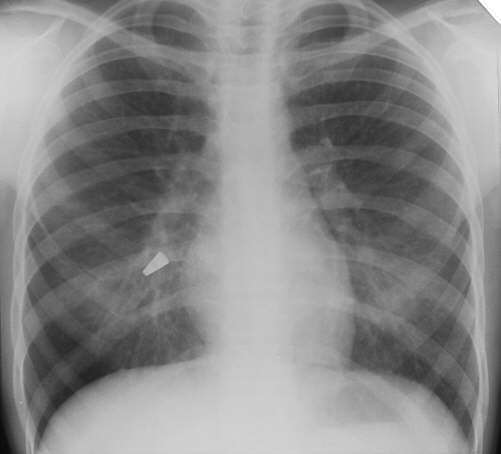

Describe the abnormality/ies

Foreign body